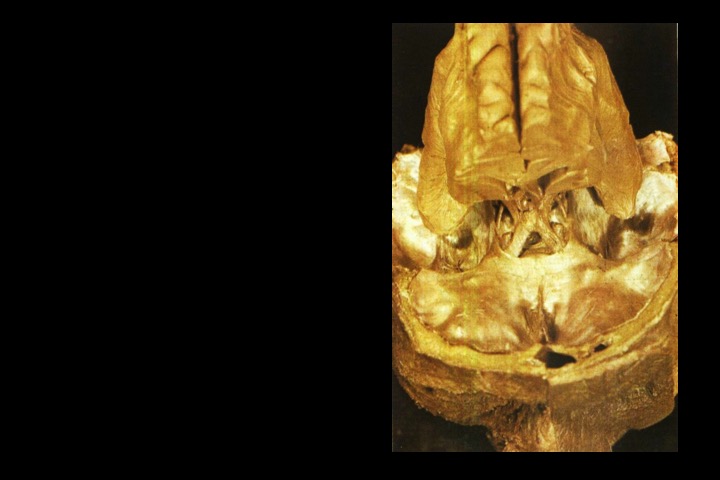

O Prof. Emérito da UFRJ Dr. Adalmir Morterá Dantas está disponibilizando através de nosso website e de nosso canal youtube (cursobom) o Museu de Neuroanatomia, no intuito de promover esta área de conhecimento junto aos estudantes de Medicina.

As figuras são apresentadas em 4 vídeos no youtube e podem ser obtidas via download clicando-se na figura em questão.